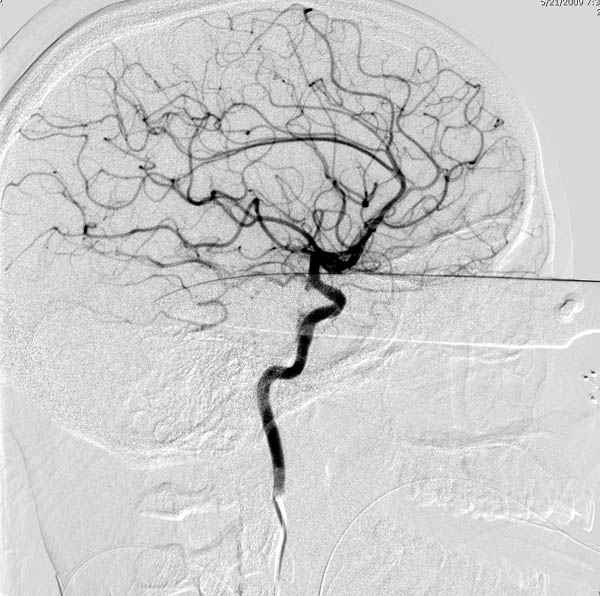

По протоколу сделаны все необходимые исследования: рентген, ангиограмма с 3Д реконструкцией, где обнаружили что все жизненно важные сосуды не задеты, даже некоторые "сидят" изгибаясь на ноже.